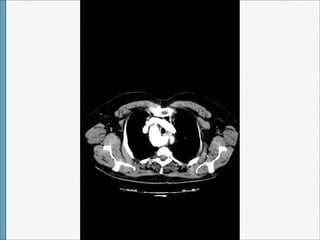

Volviendo al caso…

Tras acudir varias veces a urgencias por dolor torácico atípico (con constantes,

exploración,ECG, Bioquimica, hemograma y coagulación (incluido enzimas cardiacas)

completamente normales , se pidió interconsulta con Cardiología que citó en 2014 para

completar estudio con ecocardiograma y prueba de esfuerzo:Normales

Tto: Se le pauto Adiro 100 mg (0-1-0)

No seguimiento de síntomas disfágicos.

El ensanchamiento mediastinico superior en una rx es un

signo muy inespecífico y por ello ha de ser valorado

adecuadamente en el contexto clínico de cada paciente.

El conocimiento de estas variables anatómicas resulta de gran

interés a la hora de interpretar y orientar el diagnostico de las

posibles causas de un ensanchamiento mediastínico superior

detectado de manera incidental en las rx de tórax tanto en

asintomáticos como en sintomáticos.

Lectura de caso: Arco aórtico derecho